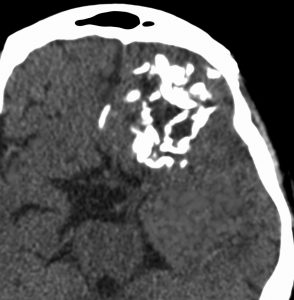

極めて高度な石灰化:脳石 brain stone

左は通常のCT,右は骨条件CTです。左前頭葉に巨大な石灰化を伴う乏突起膠腫があります。病理組織像は基本的にはグレード2です。石の塊のようにみえるので braine stoneと呼ばれ,CT eraでは oligodendrogliomaの hallmarkと言われました。